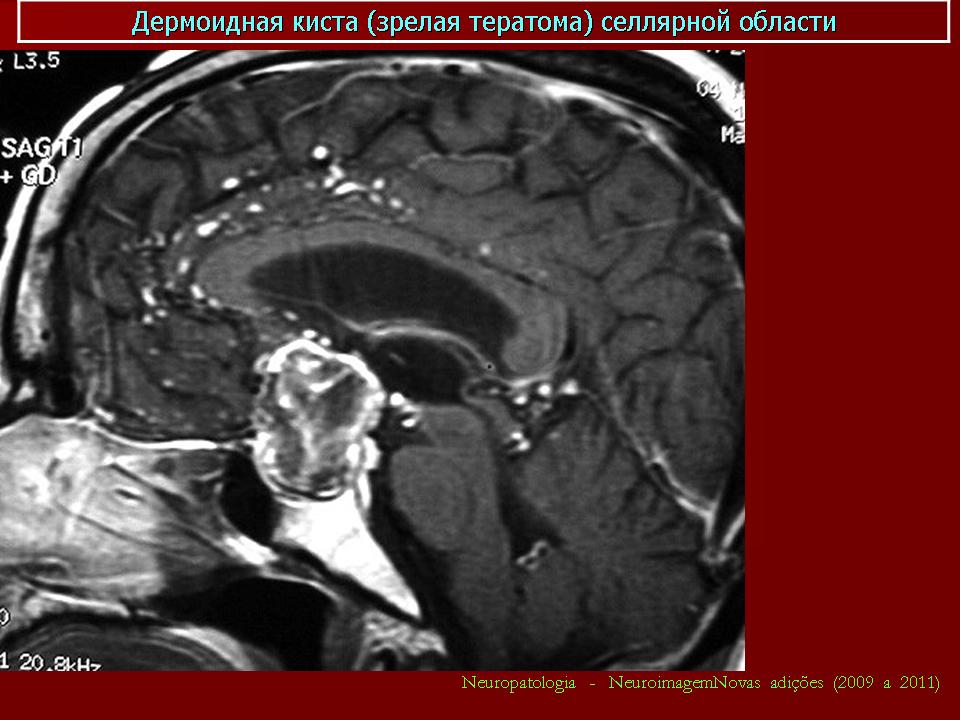

Дермоидная киста